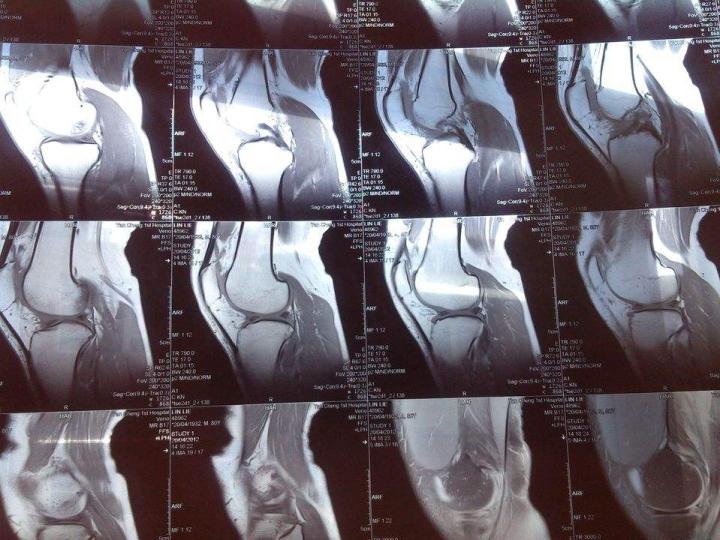

(图)膝盖核磁共振片子

健康的每一个相同器官,经过核磁共振后释放出的能量是相同的。每个器官都有一个核定健康的“能量值”。当患者完成核磁共振之后,医生正是通过比对患者的“能量值”与标准能量值的差异来判断病变与否。

还是举两个例子说明:

一、医学上有器官水肿或者器官积水这两种说法,怎样通过核磁共振判断是否水肿或者积水呢?一旦某个器官积水或者水肿,器官内的水分子肯定会增多。它共振时吸收的能量越多,释放并且被感知到的能量也越多——成像上可以通过能量异常,判断器官的水分子数量明显增多,从而确定该器官积水或者水肿。

二、器官发生病变一般意味着水分子周围环境状态和在整个器官结构当中的位置发生变化,这也会引起核磁发生共振所吸收的能量发生量变。这也是医生判断器官内部环境是否发生病变的标准之一。

核磁共振检查的范围、准确率都比X光、CT强大,这也是为什么核磁共振很贵的原因。核磁共振在骨骼、肌肉和器官的检查上都有相当的价值,并且核磁共振的核心优势是对软组织的检查更准确——这也是足球运动员肌肉拉伤、韧带损伤等疾病都拍核磁共振的原因。此外,核磁共振对颅脑、脊柱和脊髓等的解剖和病变的显示,也比CT更好。